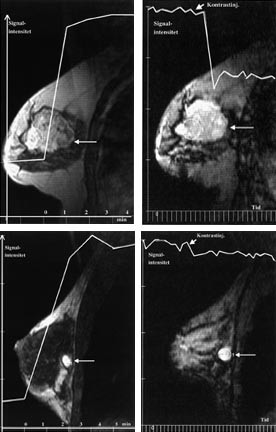

Brystkreftsvulster som er større enn 5 cm eller som vokser inn i hud eller brystvegg, behandles vanligvis med kjemoterapi eller anti-hormonbehandling før kirurgi. På grunn av problemer med å differensiere ødem og arrvev fra vitalt tumorvev er responsen på denne behandlingen vanskelig å vurdere, både klinisk og med konvensjonelle bildemetoder. Flere studier tyder på at kontrastopptak ved MR samsvarer godt med vitalt tumorvev (32, 33). Ved å registrere endringer både i kontrastopptaksmønster og tumorstørrelse er trolig MR den beste bildediagnostiske metoden for å evaluere behandlingseffekten (fig 4).